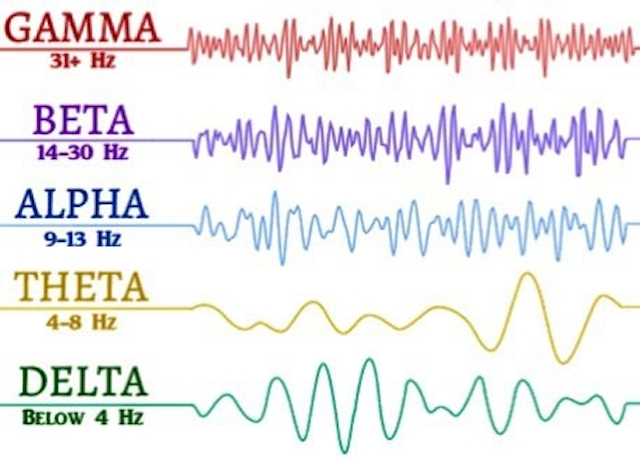

En total, los investigadores registraron unos 900 segundos de actividad cerebral antes e inmediatamente después de la muerte del paciente. Esto les permitió observar con precisión cómo cambiaban sus oscilaciones neuronales, patrones repetitivos de actividad neuronal, también conocidos como ondas cerebrales, mientras moría. Descubrieron que en los 30 segundos anteriores y posteriores al paro de su corazón se produjo un cambio inusual en la actividad de sus ondas cerebrales. "Justo antes y después de que el corazón dejara de funcionar, ocurrieron cambios en una banda muy específica de oscilaciones neuronales", afirmó Ajmal Zemmar, investigador principal y neurocirujano de la Universidad de Toronto. Estos tipos específicos de oscilaciones se conocen como ondas gamma.

Las oscilaciones neuronales se clasifican en función de su frecuencia y amplitud. Las ondas gamma tienen una frecuencia de entre 30 y 100 hertz, la más alta de todas las oscilaciones, y se observan con mayor frecuencia en el cerebro cuando las personas acceden a su centro de memoria, en el hipocampo, durante los sueños. El equipo también recopiló datos sobre otros tipos de oscilaciones durante la muerte, como las ondas delta, theta, alfa y beta. Pero fueron las ondas gamma las que apuntaron a que el hombre repetía en su cerebro recuerdos de su vida, un fenómeno conocido como recuerdo vital.

Los experimentos con ratas han demostrado que los roedores también experimentan niveles similares de oscilaciones gamma alrededor del momento de la muerte, según los autores del estudio. Por lo tanto, especulan que el recuerdo de la vida puede ser una experiencia universal compartida por la mayoría de los cerebros de los mamíferos que mueren, aunque las pruebas que lo respaldan son mínimas. El sujeto del estudio era anciano y padecía epilepsia, que se sabe altera la actividad de las ondas gamma. Esto podría significar que su actividad cerebral durante la muerte fuera diferente a la de alguien sin epilepsia. Además, no hay forma de saber si el hombre estaba realmente viendo o percibiendo sus recuerdos pasados o si sólo estaba en un estado onírico provocado por el deterioro de su sistema nervioso.